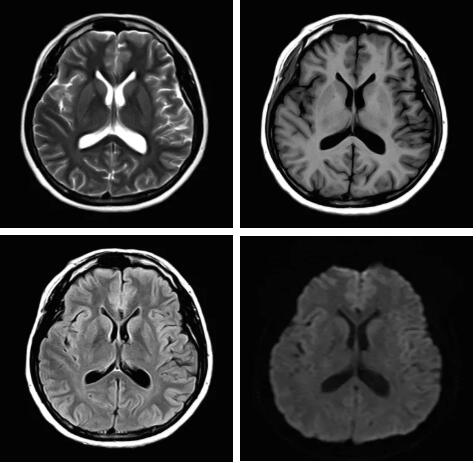

圖:Pure射頻成像鏈的優(yōu)化和改進使信噪比提升